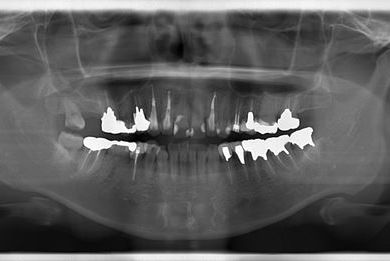

| 性別/年齢 | 女性 / 34歳 | ||||||||||||||||||||||||||||||||

| 主訴 | 現在痛みはなく、前歯の汚れを治したい。奥歯はブリッジを考えている。審美を考えているが、今治療をしたいというよりは、セラミックなど詳しいことがわからないので、計画や説明を伺いたい。 | ||||||||||||||||||||||||||||||||

| 治療方針 | 上前歯部分、セラミック治療にて審美的回復を行う。 | ||||||||||||||||||||||||||||||||

| 治療内容 | オールセラミッククラウン3本(オールセラミック用土台3本)、メタルボンドセラミッククラウン1本 | ||||||||||||||||||||||||||||||||

| 総治療費 | 562,800円 | ||||||||||||||||||||||||||||||||

| 治療期間 | 8ヶ月 |